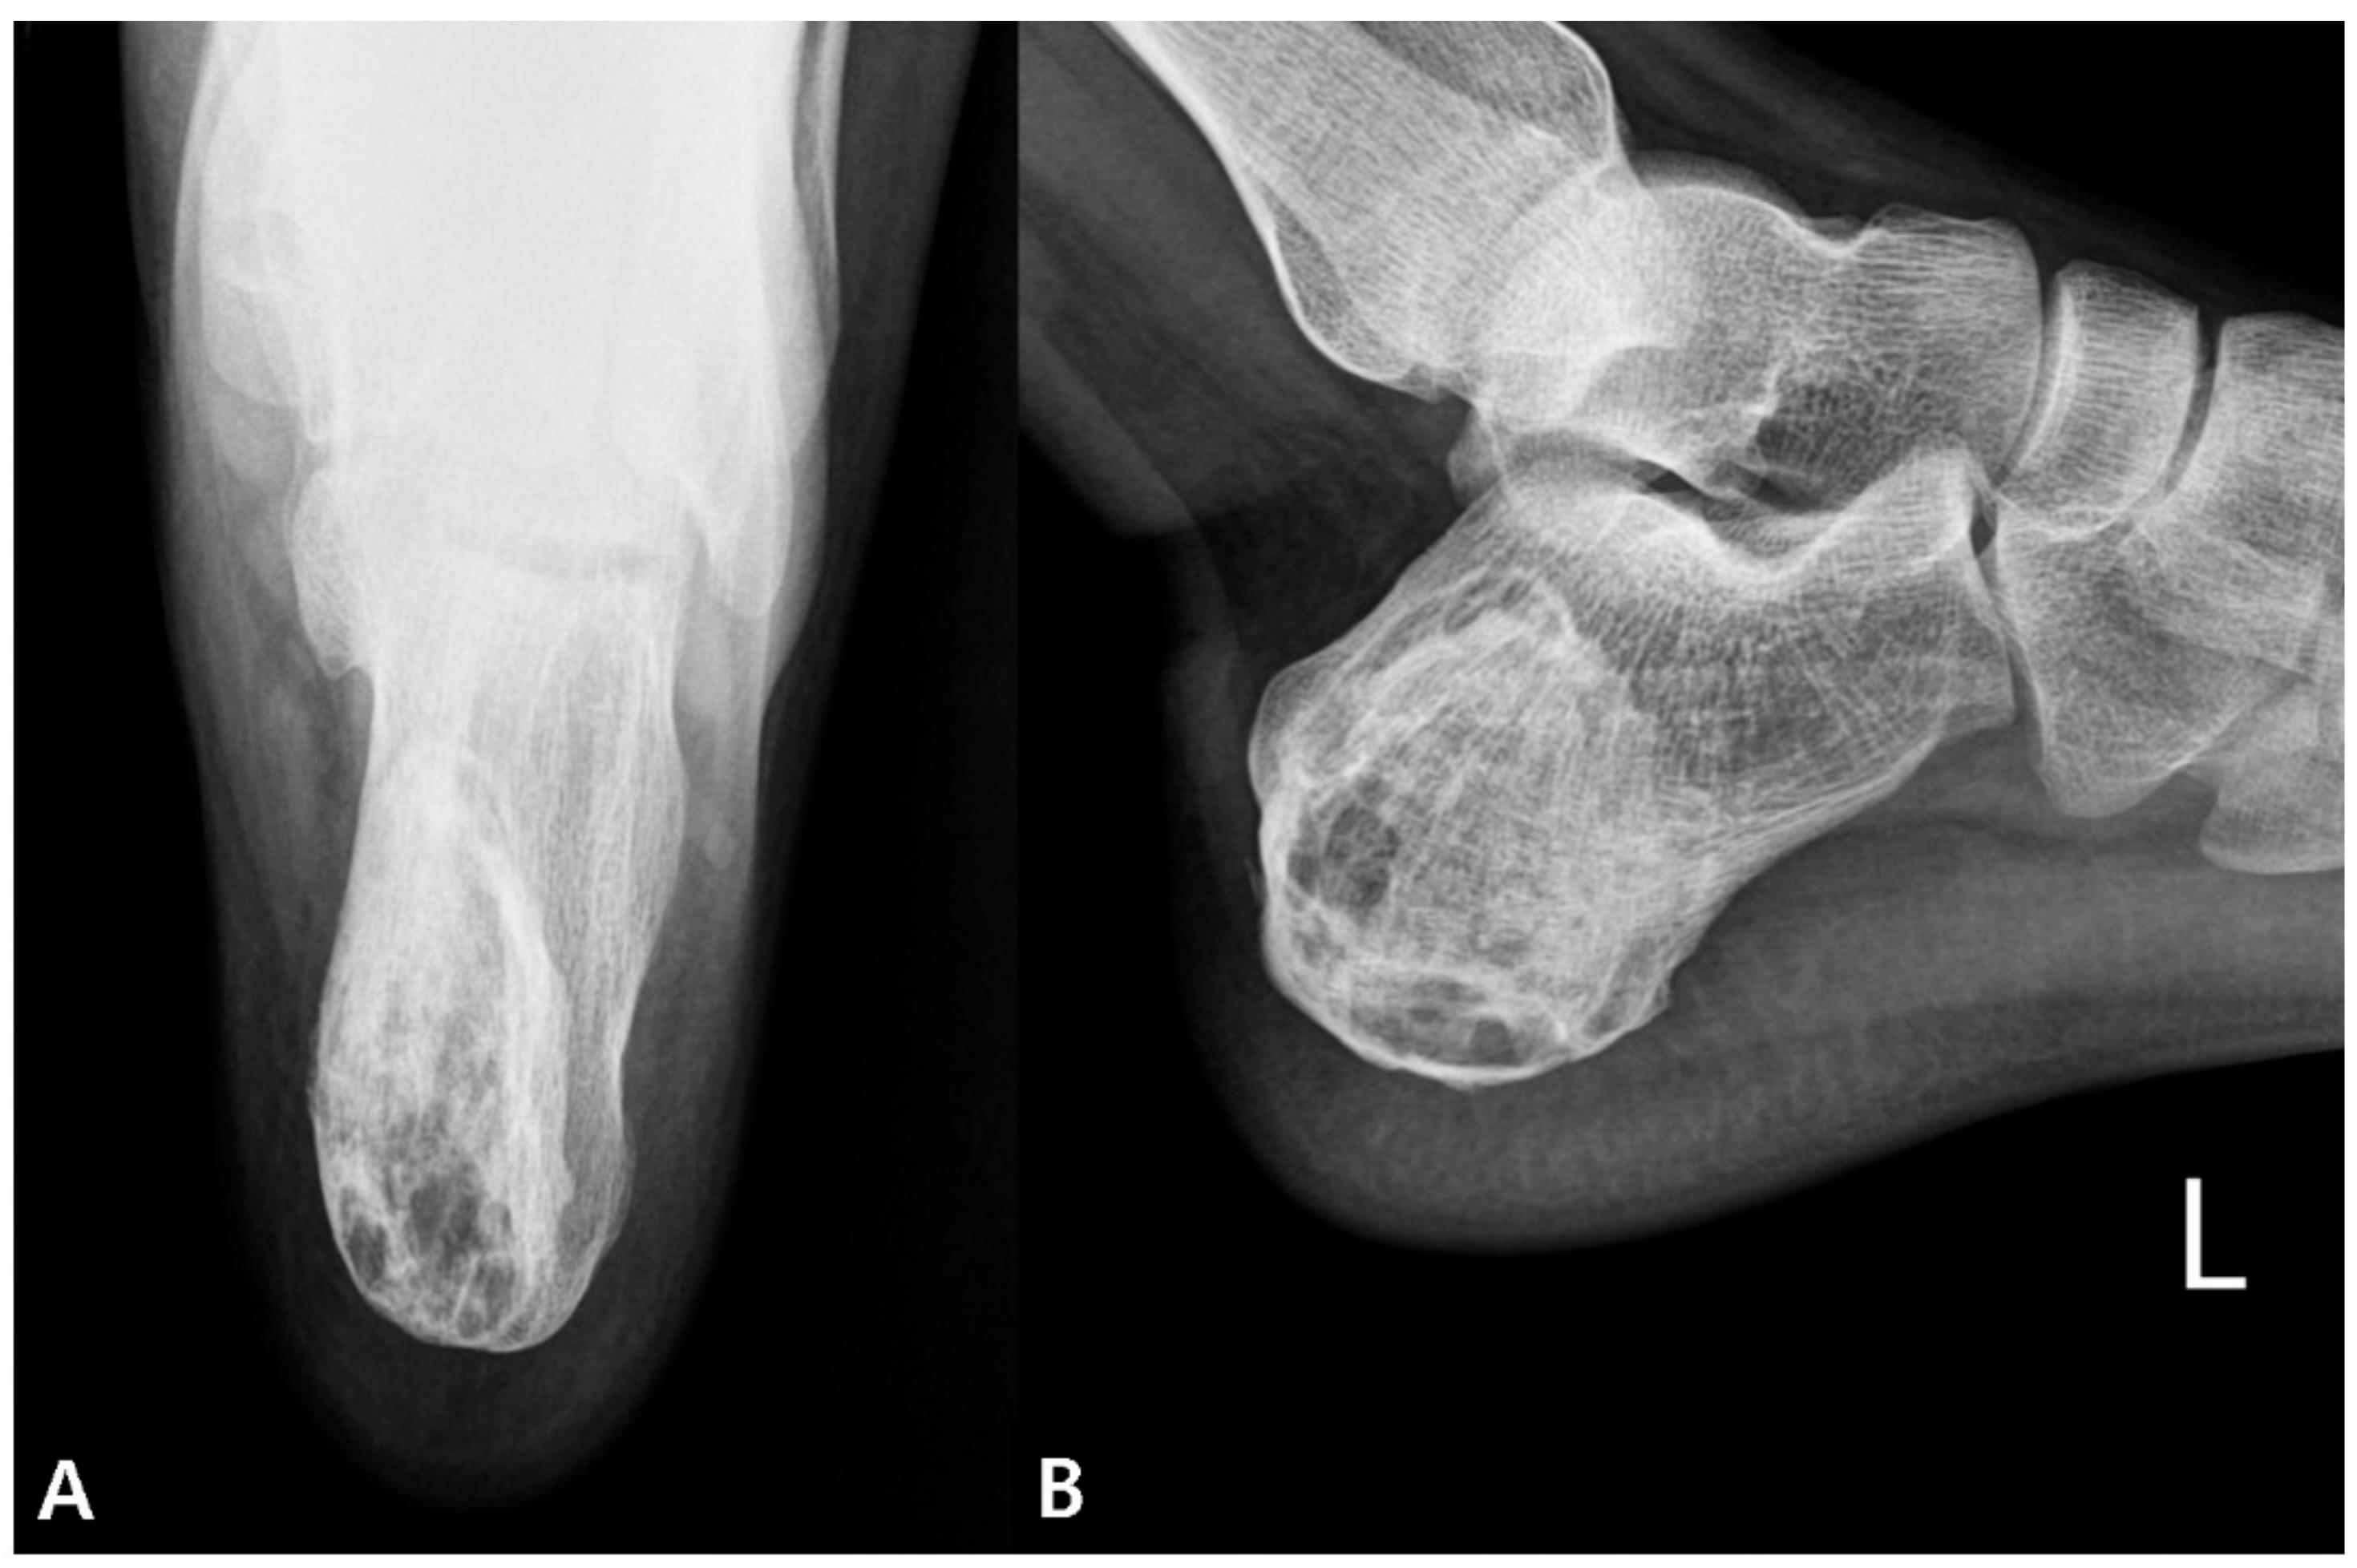

2. Case Presentation

2.1. Preoperative Evaluation

2.3. Postoperative Progression